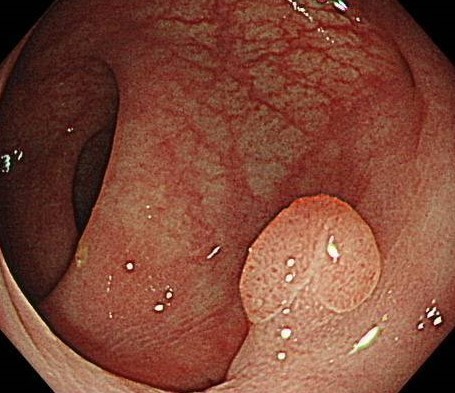

日帰り内視鏡治療

当クリニックでは大腸ポリープ・病変発見時に一度で検査・治療を行うことができます。大腸内視鏡を行ってもポリープがあると あらためて別の病院でもう一度下剤をのみ内視鏡治療を受ける必要となる施設もあります。一度で治療までできることは体力も時間も金銭的にも負担が少なくなります。

少しでも検査を受けられるみなさんの負担が少なくなるよう工夫し、当クリニックでは大腸ポリープ・病変発見時に一度で検査・治療を行うことができ、治療のあとゆっくり休むことができる体制を整えております。また遠方の方、トイレが不安な方には院内で検査前の下剤をのむ環境も整っております。一度ご相談ください。